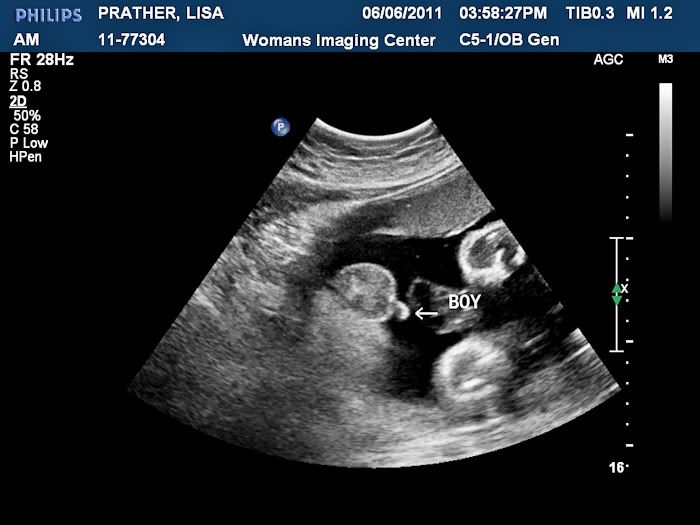

We had an ultrasound today and got to see our baby boy! It was so wonderful to see him, but even better to find out that he is still perfect. He weighs 4 pounds and 11 ounces right now!

Cute little feet that like to kick Mommy!

We may have a future gymnast on our hands. His foot is right above his nose!